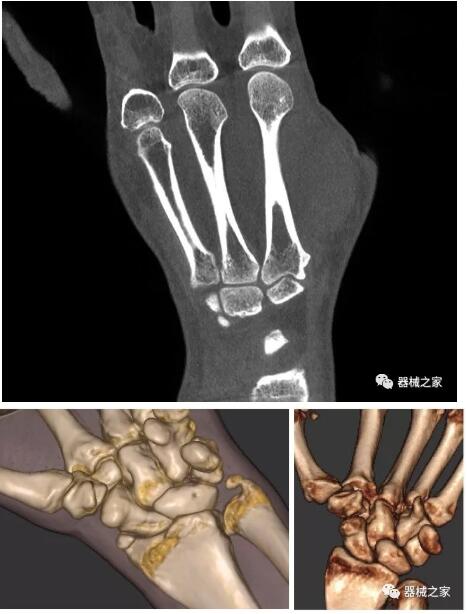

另外一款被稱為世界上最小的CT,它的重量僅300磅,不僅能夠掃查足部,還可以檢查膝蓋和上肢等。

與上面介紹的CT一樣,它同樣具有輻射低、占地空間?。?3*36)的特點,隨開隨用(支持直接接入墻上的插座)。

這款CT使用非常方便,通過上下移動保持與患者的手臂或者雙腿齊平,掃描快速,僅需要30秒左右就可以完成掃查。

以上介紹的CT均來自國外同一家公司,這些CT均配置了可視化軟件,可以進行切片、3D重建以及大型CT附帶的所有典型的操作功能。

以下是這些“特立獨行”的CT所拍出來的圖像: